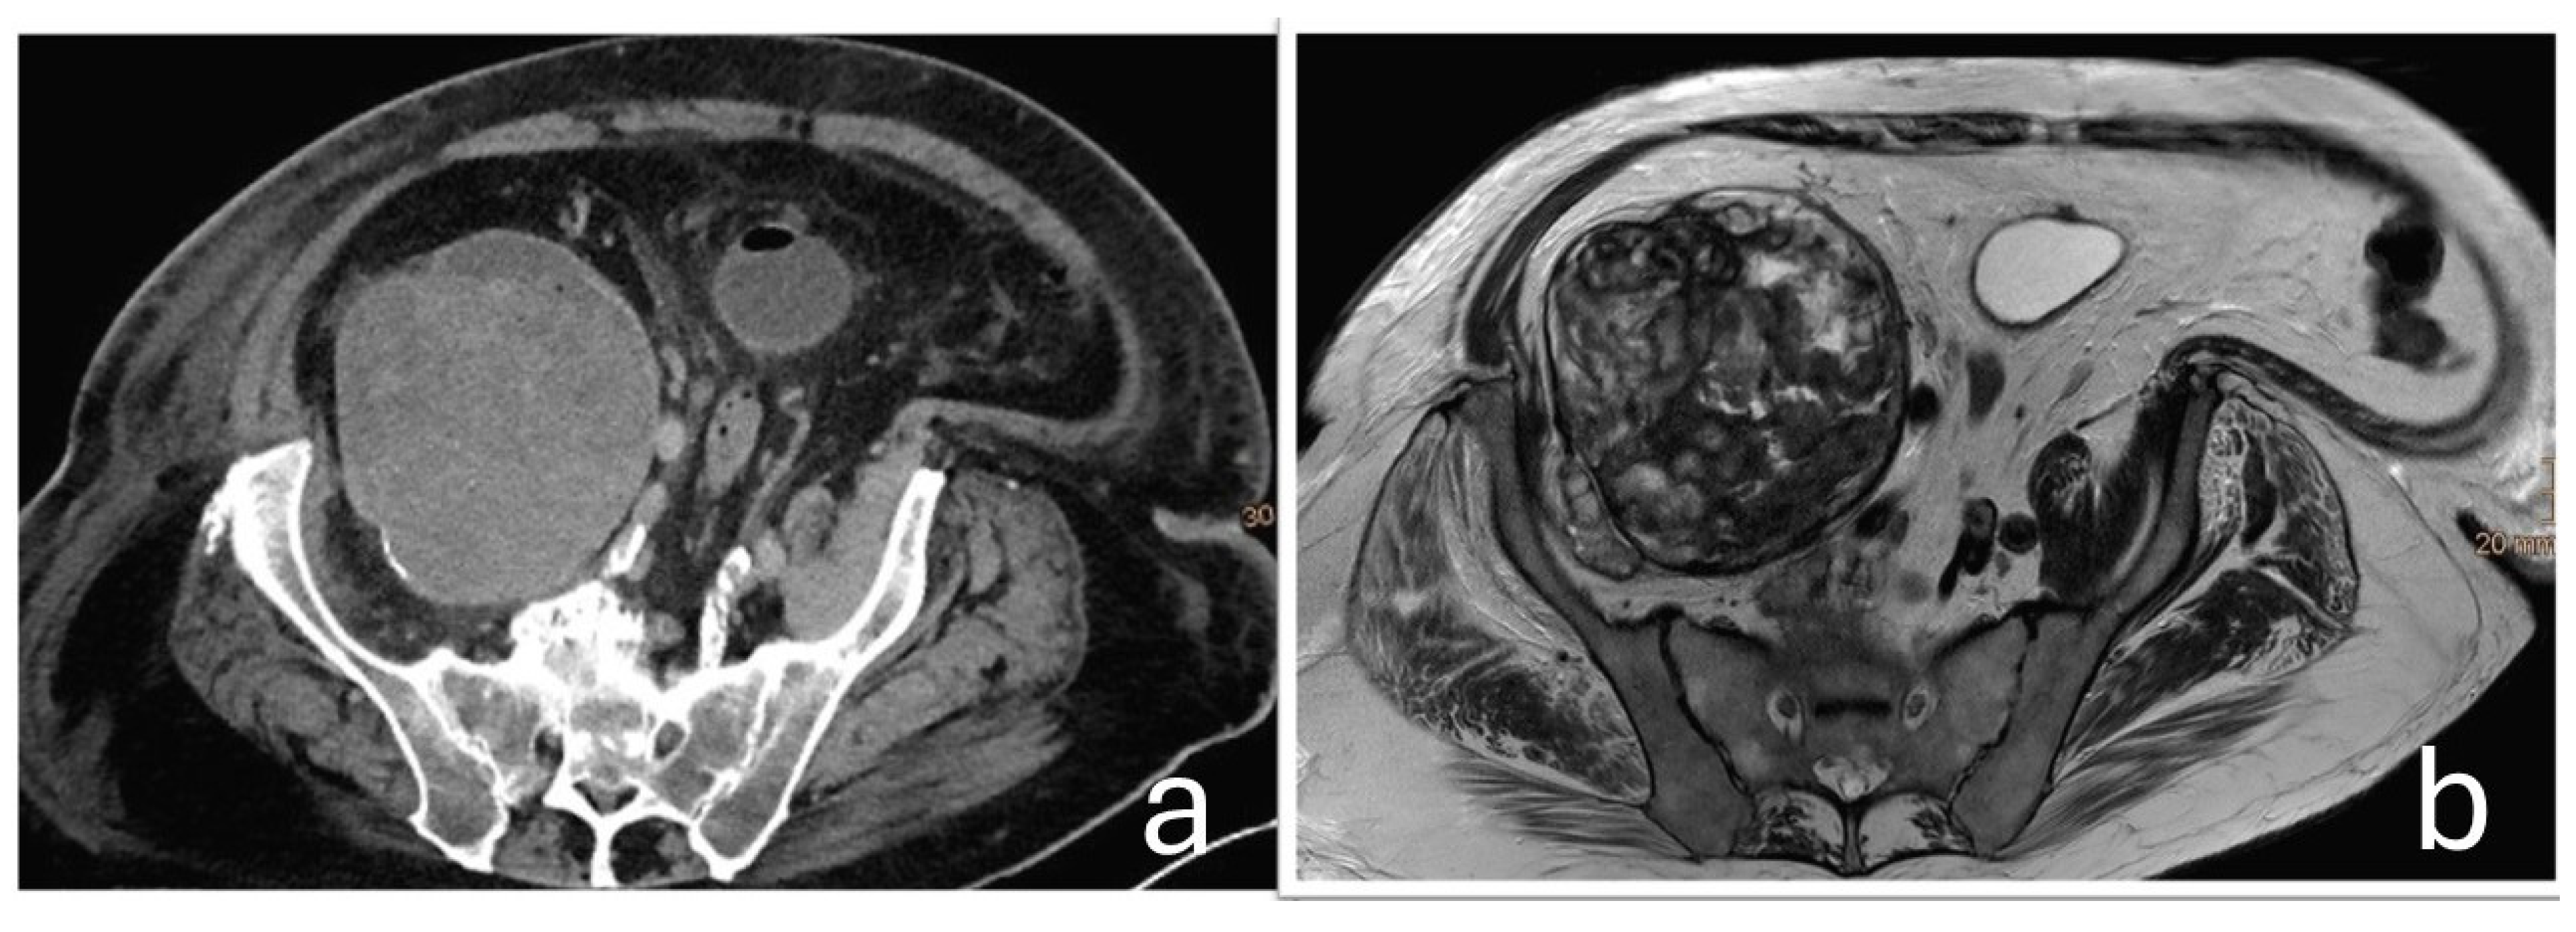

At the time of orthopedic examination, the hip joint was functional and non-painful. However, by reconstructing additional imaging planes from the existing CT and MRI datasets, the close anatomical relationship between the hip joint and the tumor mass could be visualized more clearly. (Figure 4).

Figure 4. Additional reconstructed CT (a) and MRI (b) images demonstrate the close anatomical relationship between the pelvic mass (+) and the distally located total hip arthroplasty (*). The red and blue lines in the cross-sectional images indicate additional calculated planes that show the spatial proximity between the implant and the mass.